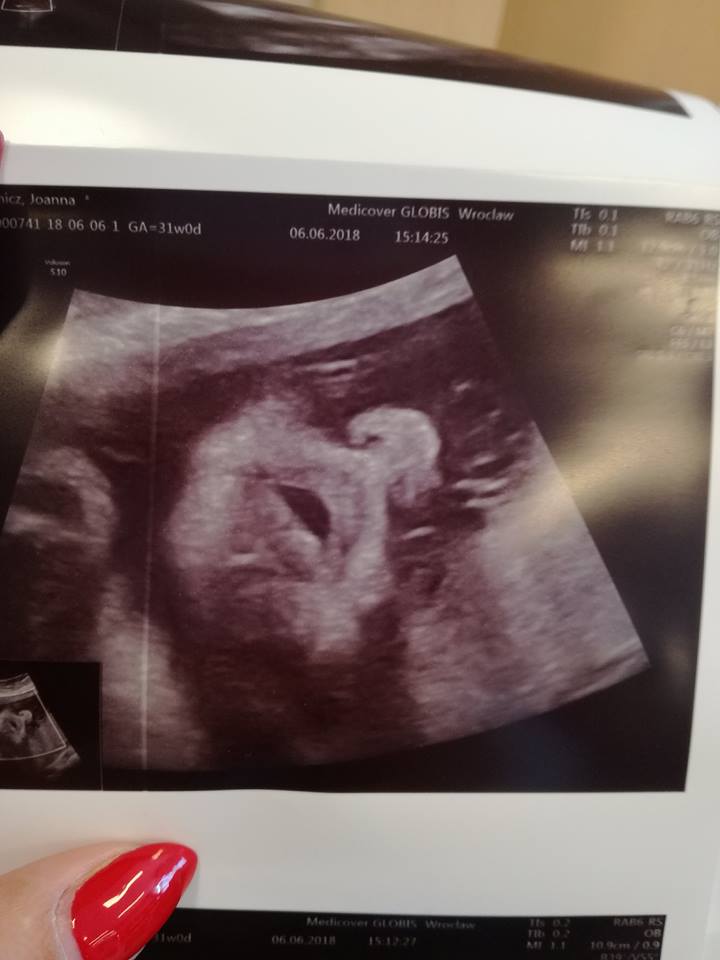

Miałam trochę stresów przez pierwsze dwa dni, po podróży mega skurcze mnie złapały, dwie godziny lezałam, miałam już bóle takie mocne miesiączkowe i częste stawianie się brzucha, że jak raczej podchodze spokojnie do temtu ciązy tak sama się przestraszyłam, do tego plamienie brązowe i na drugi dzień trochę krwi. Nabrałam magnezu i nawet nospę pierwszy raz, przeszło, ale trwało zaskakująco długo. także te pierwsze dwa dni mega stres a potem tez bo jednak bałam się że znowu coś się zadzieje. Teraz już chyba bym się nie zdecydowała na taką podróż, jednak to zbyt męczące. U nas wszystko ok, byliśmy na prenatalnych, mała jest dość mała bo w 31+1 ważyła 1592g ale lekarz powiedział że w normie wszystko. Mam też zdjęcie piękne buziaczka to tez się pochwalę. Kopia synka będzie